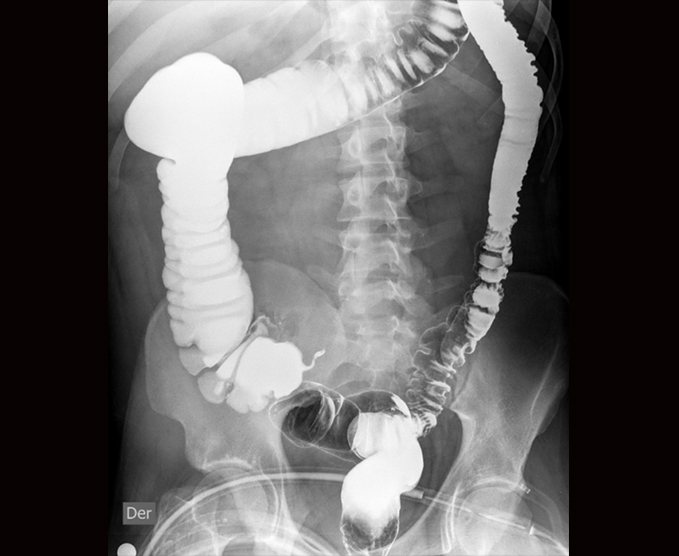

Algunos de nuestros estudios contrastados.

- Colon por enema